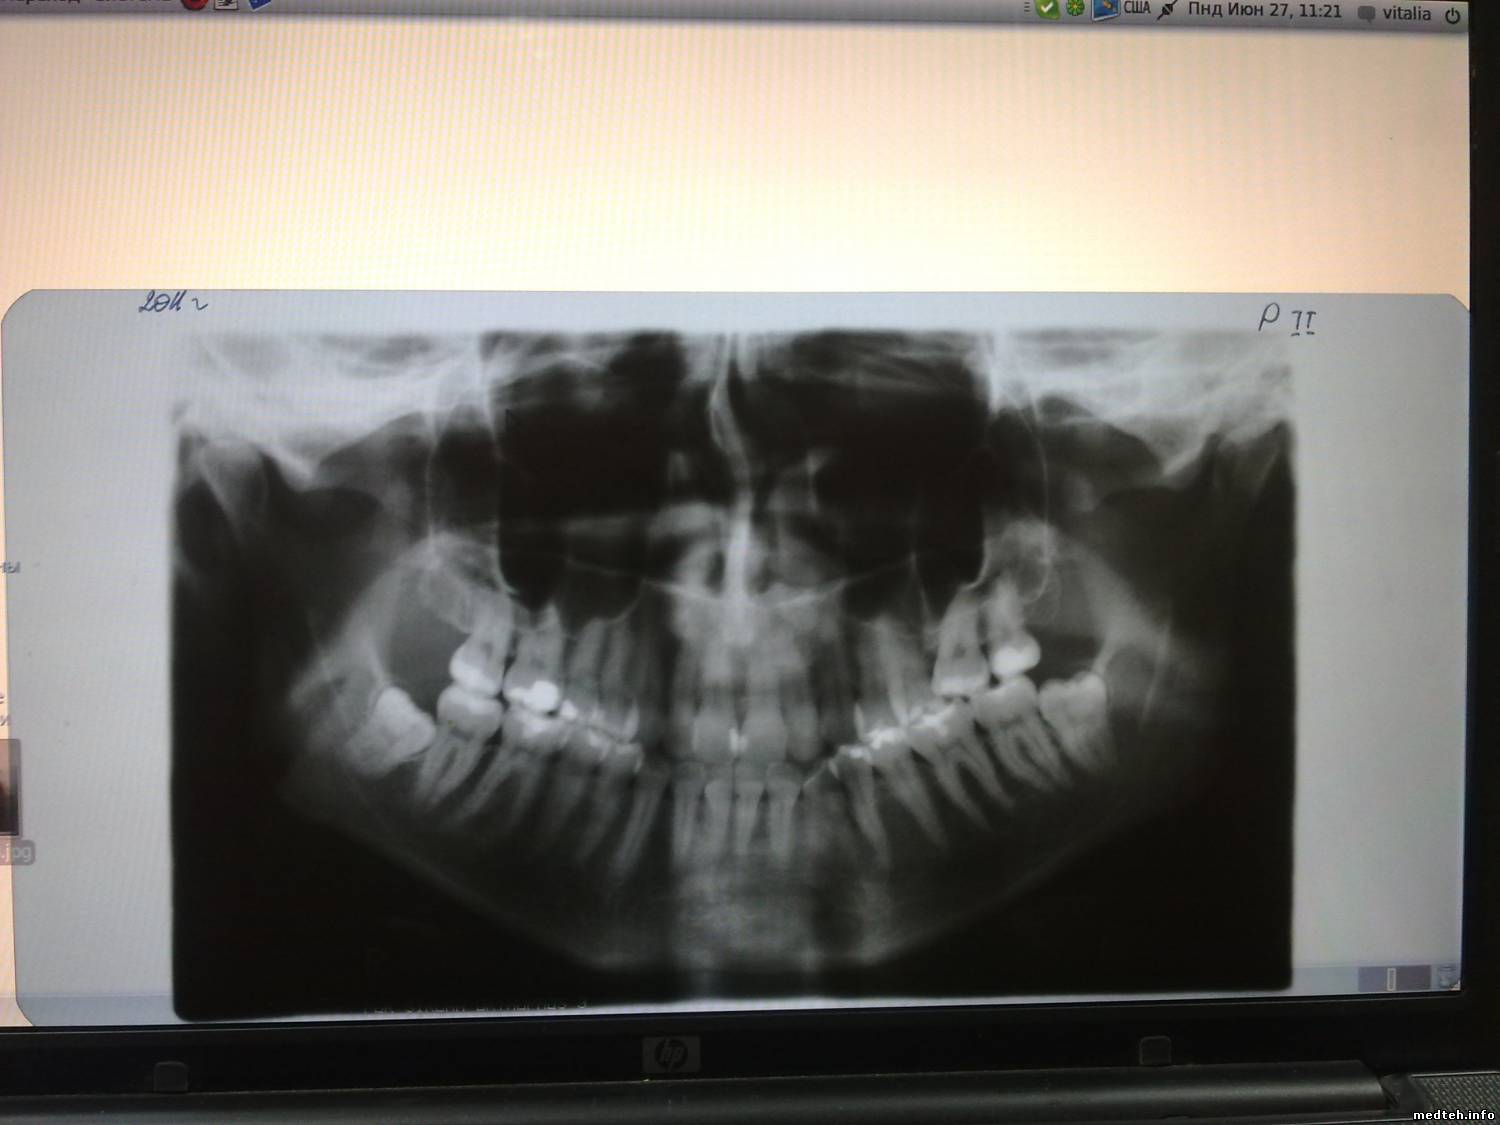

Vitaly63Дата: Понедельник, 27.Июн.2011, 11:35 | Сообщение # 14

снимки стали онформативны, но на программе 11, при 1,3-кратном увеличении рамки вообще по 3,5 см. и сам снимок аналогичен 1 программе, только "обгрыз" края. может у кого-нибудь есть какие нибудь мысли, поделитесь пожалуйста.

8772354.jpg (78.0 Kb) · 3303867.jpg (92.7 Kb)